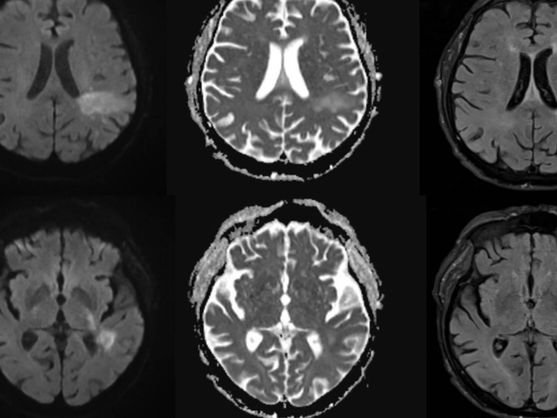

Sin embargo, en ciertos casos, puede mutar y desencadenar una enfermedad grave conocida como leucoencefalopatía multifocal progresiva.

Esta patología afecta directamente al sistema nervioso central, provocando:

- Destrucción de la mielina, clave para la transmisión nerviosa

- Alteraciones del habla y la visión

- Debilidad muscular y confusión

- Convulsiones y deterioro cognitivo progresivo

👉 El cerebro pierde su capacidad de comunicación interna.

Las pruebas confirmaron lo inesperado:

presencia del virus JC en el líquido cefalorraquídeo y lesiones cerebrales compatibles con LMP.